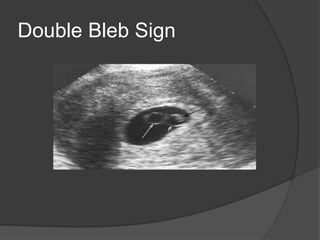

 “ Double Bleb “ sign : yolk sac and amniotic

sac and the embryo is in the amniotic sac

Diamond ring Sign

Double Bleb Sign

The Embryo  Firstseen as a focal thickening in the yolk sac  “ Diamond ring Sign”: Embryo appears as the echogenic (diamond) on top if the yolk sac (ring)  “ Double Bleb “ sign : yolk sac and amniotic sac and the embryo is in the amniotic sac  Distinct embryo with cardiac activity is seen by 5-6 weeks after LMP and a CRL of 5 mm is the discriminatory value of the presence of cardiac activity known as the “ 5 Alive “ rule.